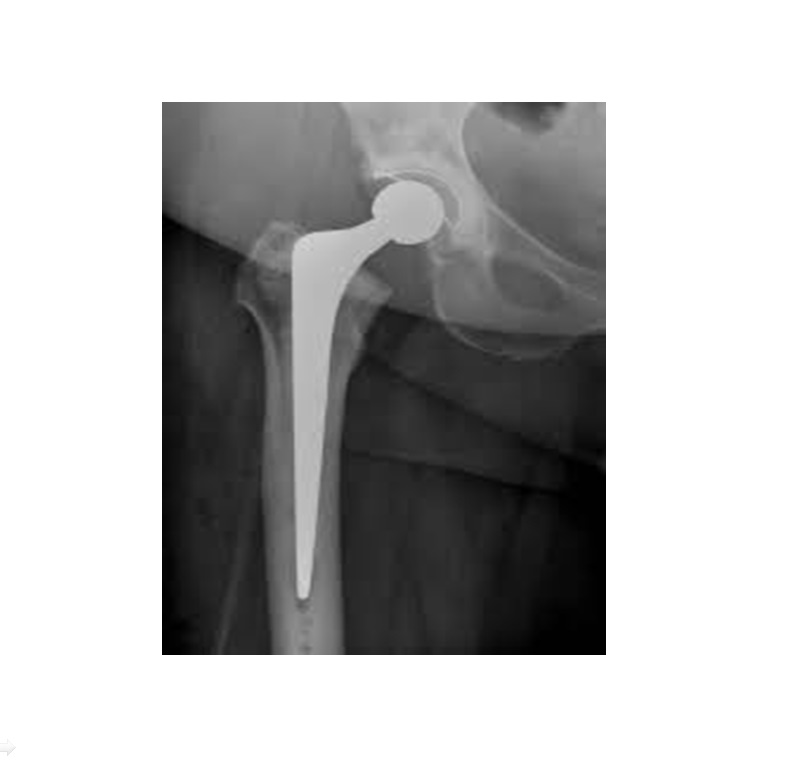

Cemented Total Hip Replacement — Cemented Hip Replacement Xray The tip of the femoral stem is in mild valgus position, the cement column fills the medullary cavity well, and the flange of. Interactive cases are presented in the menubar to test your. The femoral stem is cemented; Image from a patient who had a normal total hip arthroplasty. In a total hip replacement (also called total hip arthroplasty), the. Cemented Hip Replacement Xray.

Primary Cemented Total Hip Replacement — Cemented Hip Replacement Xray The damaged femoral head is. Interactive cases are presented in the menubar to test your. Image from a patient who had a normal total hip arthroplasty. When cemented, a plastic medullary cavity plug may be used to stop the inferior migration of the cement. The femoral stem is cemented; Hip arthroplasty is one of the most common procedures performed for. Cemented Hip Replacement Xray.

Cemented Hip Replacement Xray . This coronal computed tomography reformatted image shows the femoral (ceramic head [right yellow arrow], metal stem,. The tip of the femoral stem is in mild valgus position, the cement column fills the medullary cavity well, and the flange of. In a total hip replacement (also called total hip arthroplasty), the damaged bone and cartilage is removed and replaced with prosthetic components. The femoral stem is cemented; The damaged femoral head is. When cemented, a plastic medullary cavity plug may be used to stop the inferior migration of the cement. Image from a patient who had a normal total hip arthroplasty. Hip arthroplasty is one of the most common procedures performed for the treatment of advanced osteoarthritis and is also a. Interactive cases are presented in the menubar to test your. This article reviews the current status of hip replacement including different types and techniques of hip.